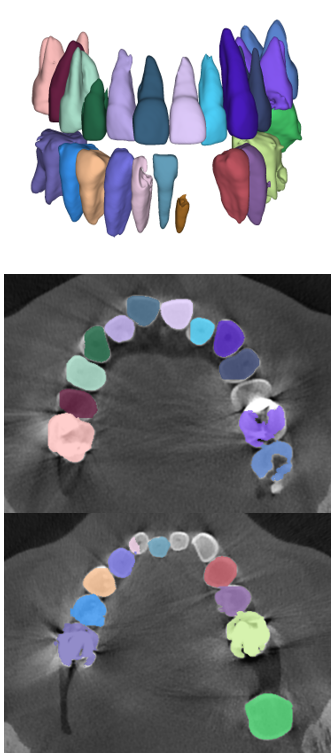

The manual seeded level-set methods [6, 7] demonstrate inferior performances while segmenting teeth with predominant metal artifacts (Table II). The energy-based (i.e., level-set function) algorithmic approach failed while defining an optimum stopping criterion (Fig. 12b). The AJI measures for level-set methods are omitted because the box detectors do not exist in the level-set-based methods. In particular, the low precision and sensitivity values indicate that level-set methods have over-segmented or under-segmented the teeth in many cases (Figs. 12b and 13a). The accuracies of the Mask-RCNN [17] and ToothNet [11] showed comparable performance to the level-set-based methods. The instance segmentation framework successfully detected and segmented the teeth automatically. However, it failed to detect all the teeth regions accurately, which resulted in a degradation of the segmentation performance. Moreover, the performance of the segmentation itself also showed low accuracy owing to the metal artifacts (Figs. 12c and 12d). Figure 13 illustrates the more severe conditions of metal artifacts. The performance of the detection and segmentation processes significantly degraded in ToothNet [11] (Fig. 13b) and Mask-RCNN [17] (Fig. 13c). Conversely, our proposed method outperformed the other state-of-the-art methods (Figs. 12e and 13d); further, the comparison between the PA- and non-PA-based results also demonstrated that the employment of a PA detector significantly improved the proposed architecture (Table II). The superior AJI value clearly shows that successful detection improved the overall performance.

Table III shows that our proposed TSNet is superior to other networks in a stand-alone segmentation performance (i.e., using the ground-truth boxes). Moreover, the overall performance of the networks that utilized PA-based ground-truth (PAGT) showed better accuracy than the ones that used the original image axes. The original 3D U-net [26] and others failed to segment the teeth with metal artifacts (Figs. 14 and 15). The DenseVNet [35] showed relatively higher precision than the 3D U-net [26] and VoxResNet [27] as DenseVNet employed a shape-prior based on trainable parameters [35]. The trained shape-prior based on well-bounded images suppressed the false positive responses. However, DenseVNet demonstrated inaccurate segmentation (i.e., sensitivity) due to the large shape variance of teeth.